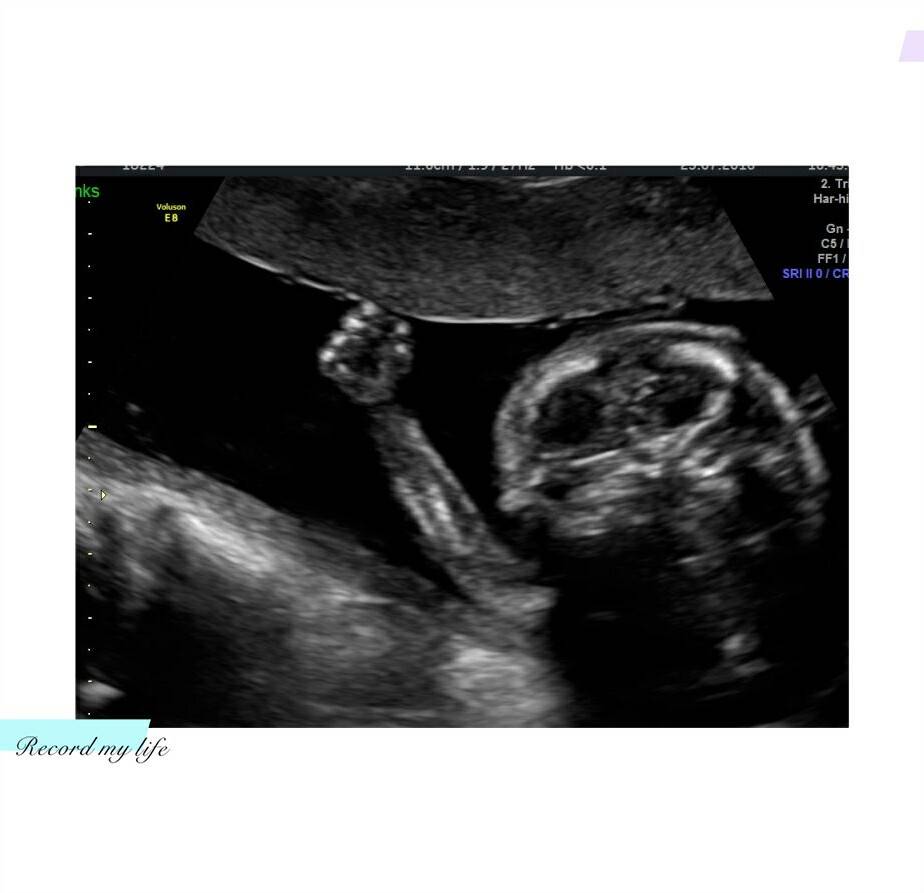

宝宝十九周了,今天去做B超医生说是个男宝宝。不知道性别的时候我和丈夫一直期望是个男宝,可是真的是男宝我又没有太高兴,觉得啊呀怎么不是女宝。这样就不能给他买漂亮裙子了。不过哪种情况我都会觉得有点失望吧,总觉得像缺少了什么。

最重要的是宝宝很健康,在肚子里活跃得很。已经开始感到隐隐的胎动了。B超里看见小拳头握得紧紧得怪可爱的。